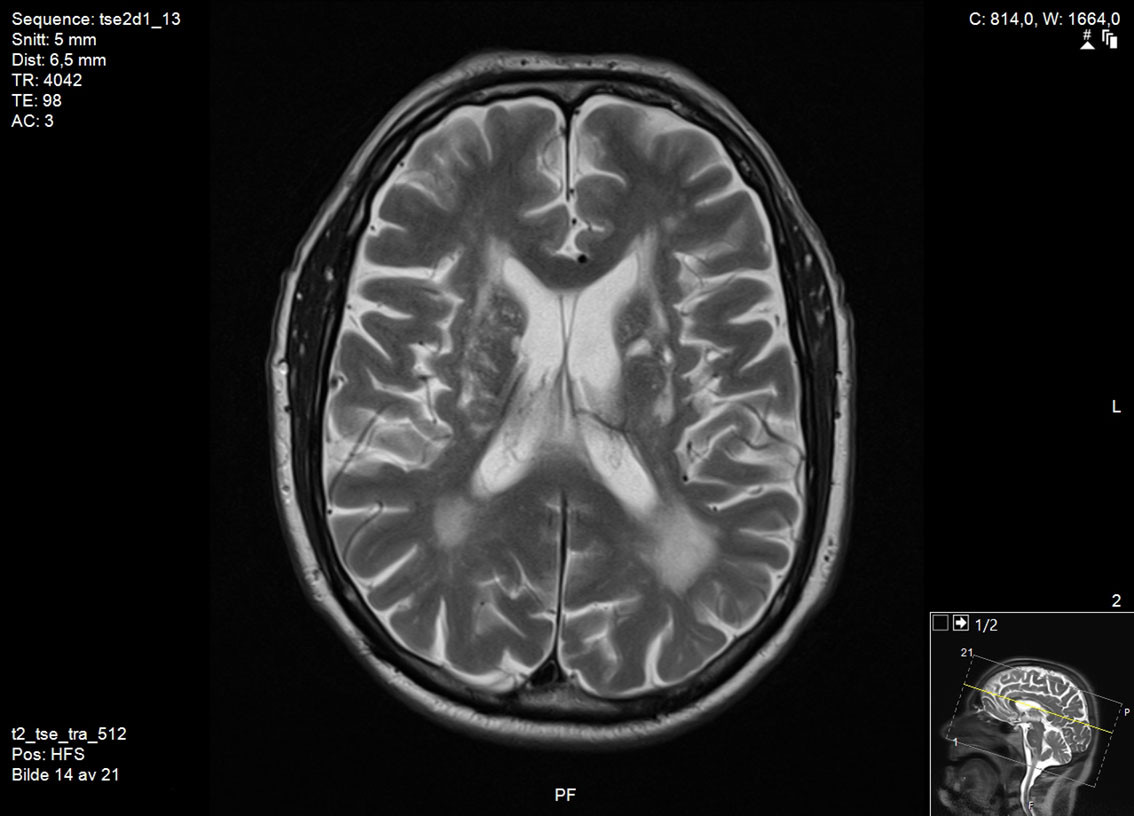

Det er ingen allment vedtatte retningslinjer for diagnostisk avklaring av vaskulær parkinsonisme, men basert på kliniske funn og patologi har Zijlmans og medarbeidere foreslått følgende kriterier: a) parkinsonisme, b) cerebrovaskulær sykdom påvist ved MR eller CT og c) en sammenheng mellom a) og b), enten i form av akutt hemiparkinsonisme fra infarkt eller blødning i den nigrostriatale banen (subtype 1) eller småkarsykdom i hvit substans med en gradvis utvikling av parkinsonisme (subtype 2) (15). Som regel er MR av hjernen nødvendig for å avgjøre om det foreligger skade i den nigrostriatale banen (figur 1) eller småkarsykdom i hvit substans (figur 2). CT av hjernen er mindre egnet for å stille diagnosen på grunn av lavere sensitivitet for lakunære infarkter og småkarsykdom (5).